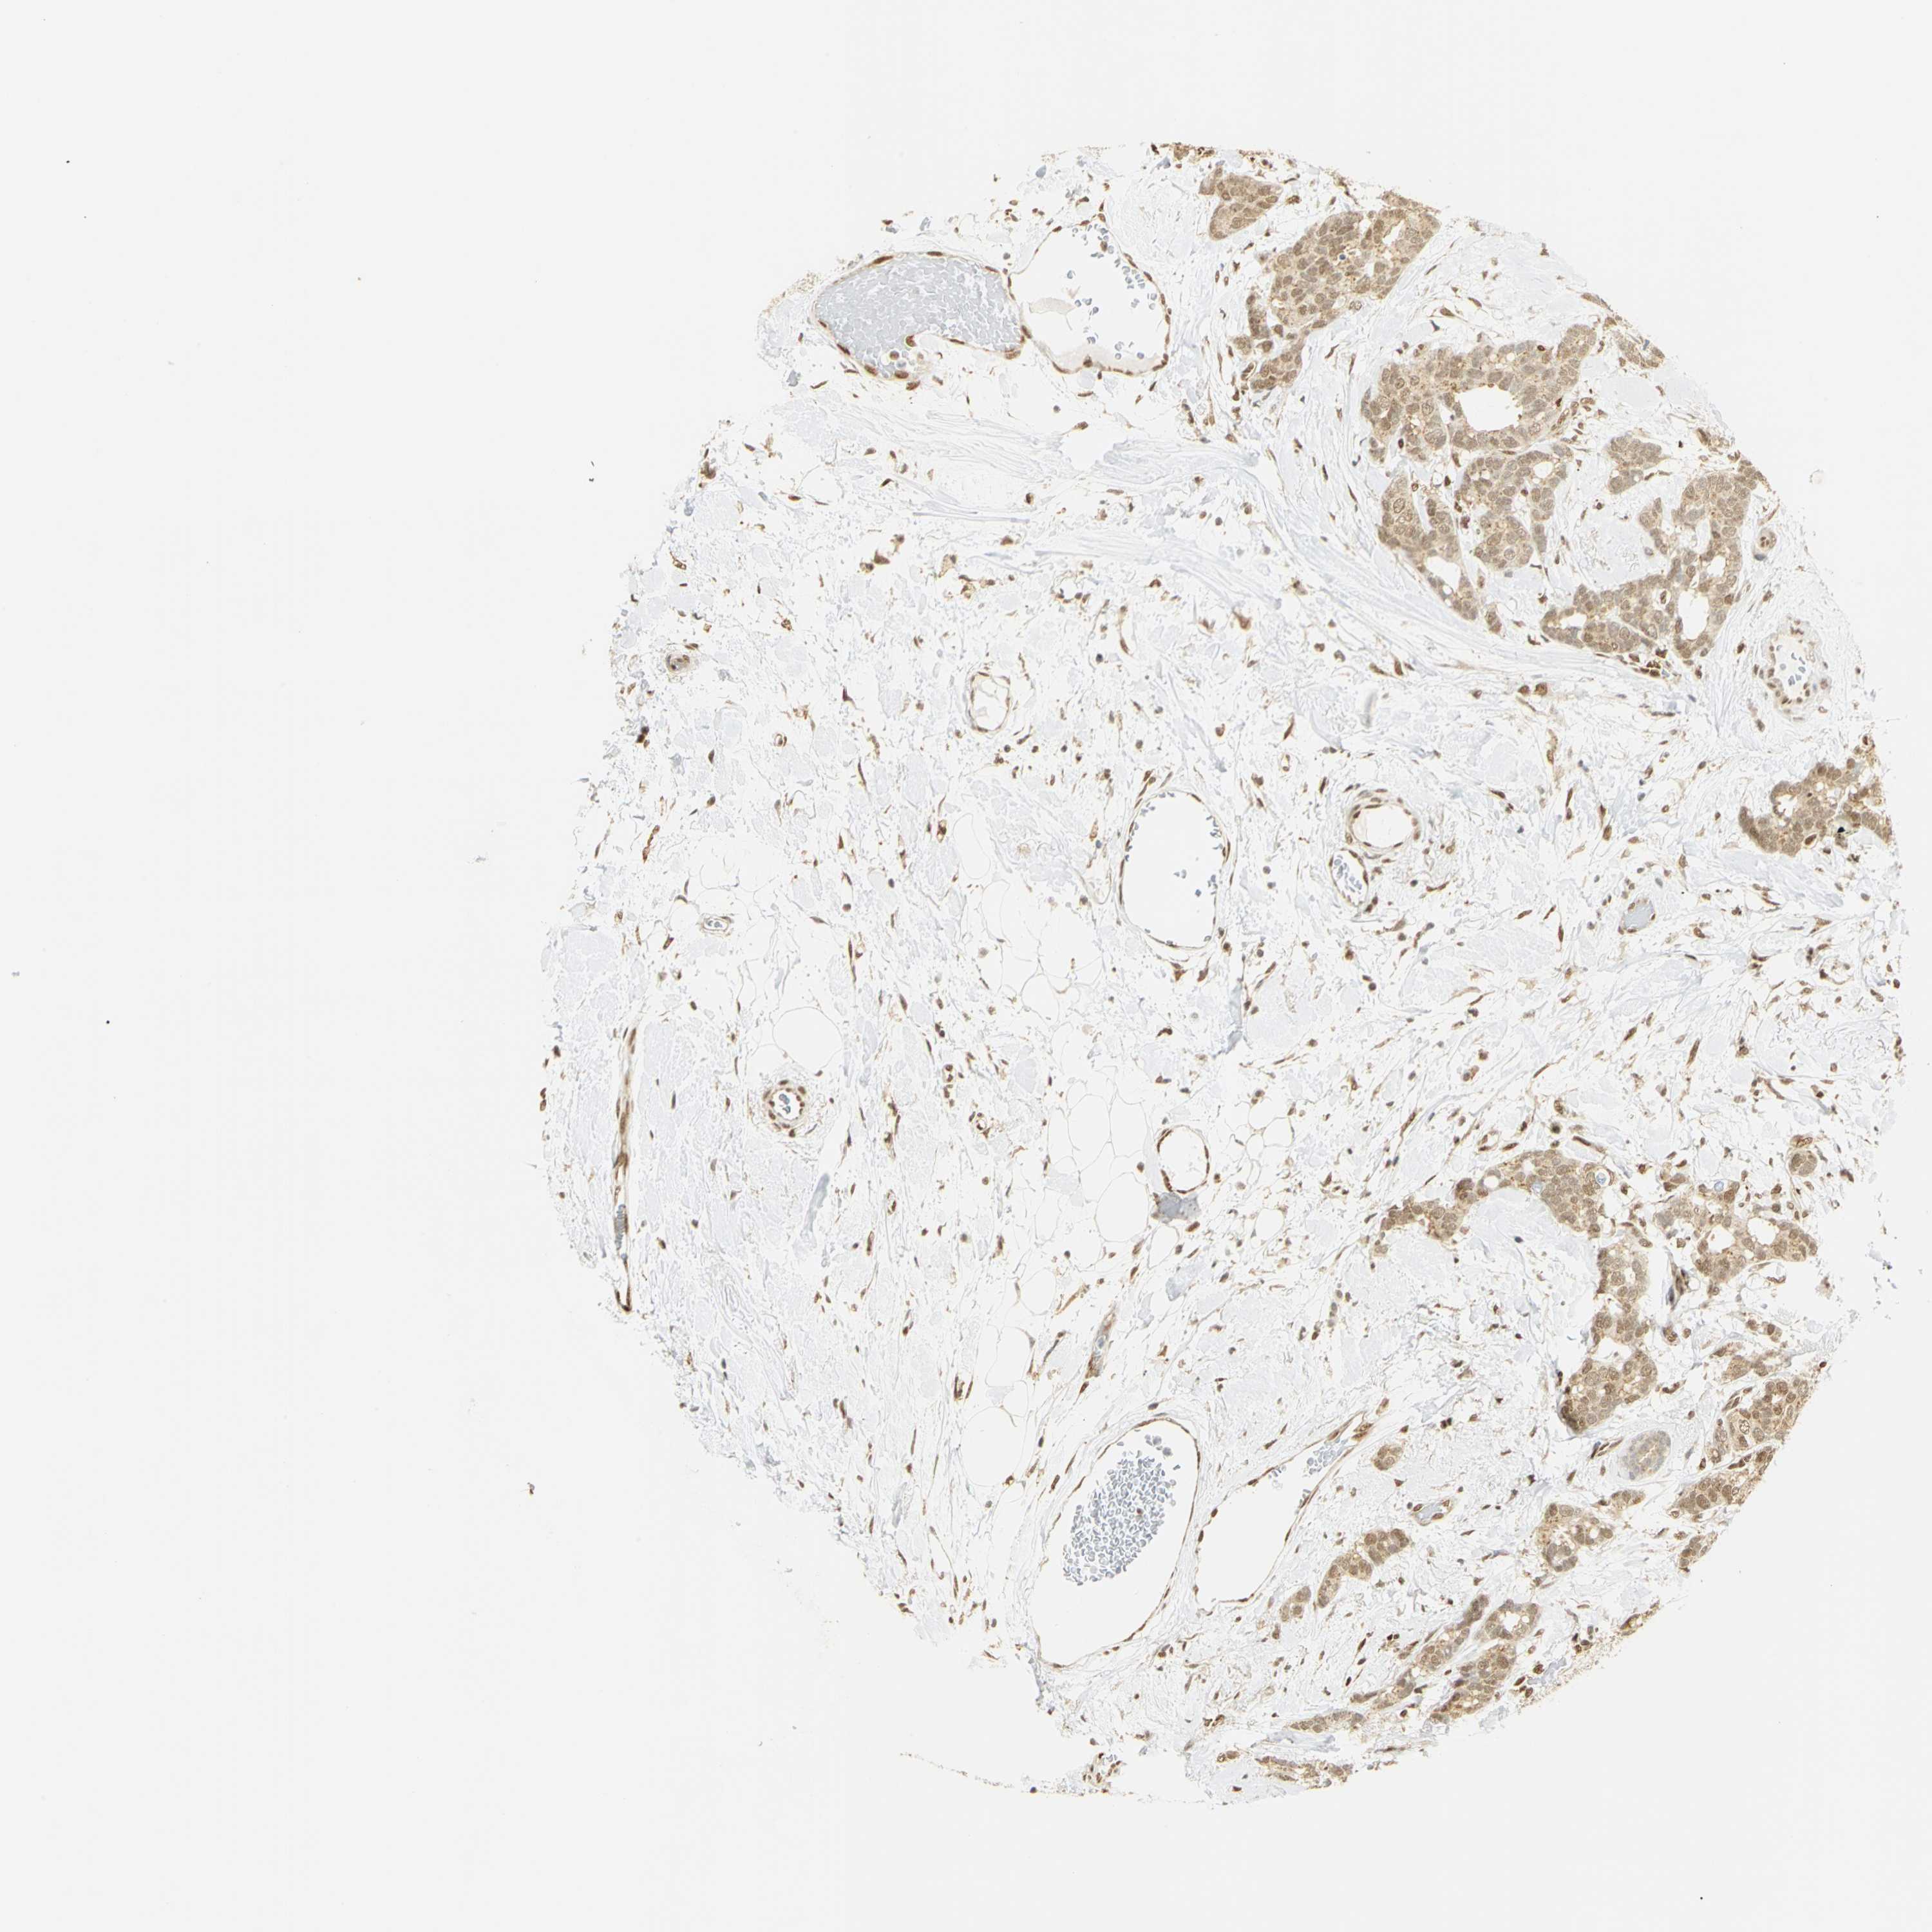

BRCA TCGA BRCA VALIDATION PROTEIN EXPRESSION